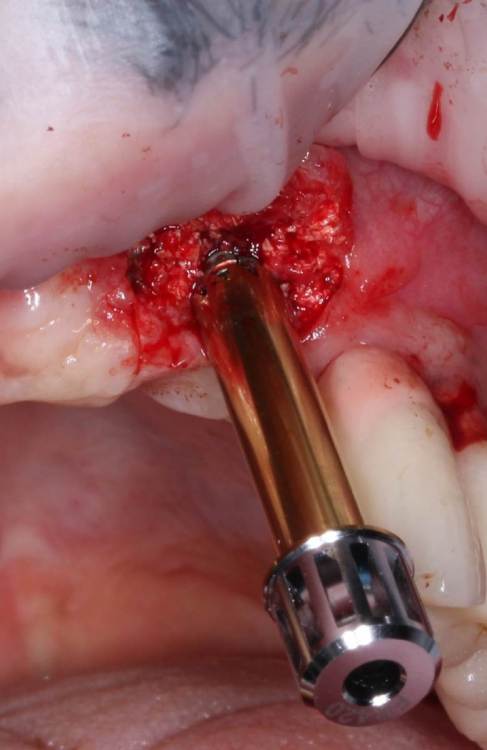

АнтонТЛТ Опубликовано 4 июня, 2021 Поделиться Опубликовано 4 июня, 2021 Жил да был имплантат 3.5мм, прижимался хорошо вместе с поджсаженной костью. Но в один момент ортопед со злобным техником решили его запротезтровать неоригинальным тибейсом в составе цирконевого моста. Имплантату это не понравилось и он решил, что ему пора на покой. И сделал себе харакири. А чтобы не сильно травмировать пациента, было решено удалить винт и имплантат. Затем сразу же поставить имплантат чуть короче и немного потолще. Время работы 50минут с учётом фотографий. 3 Ссылка на комментарий

АнтонТЛТ Опубликовано 4 июня, 2021 Автор Поделиться Опубликовано 4 июня, 2021 1 час назад, Irouil сказал: Винт, насколько я понимаю, удалялся реверсивным сверлом. А чем удалялся сам имплант? Fr-kit neobiotech 1 Ссылка на комментарий